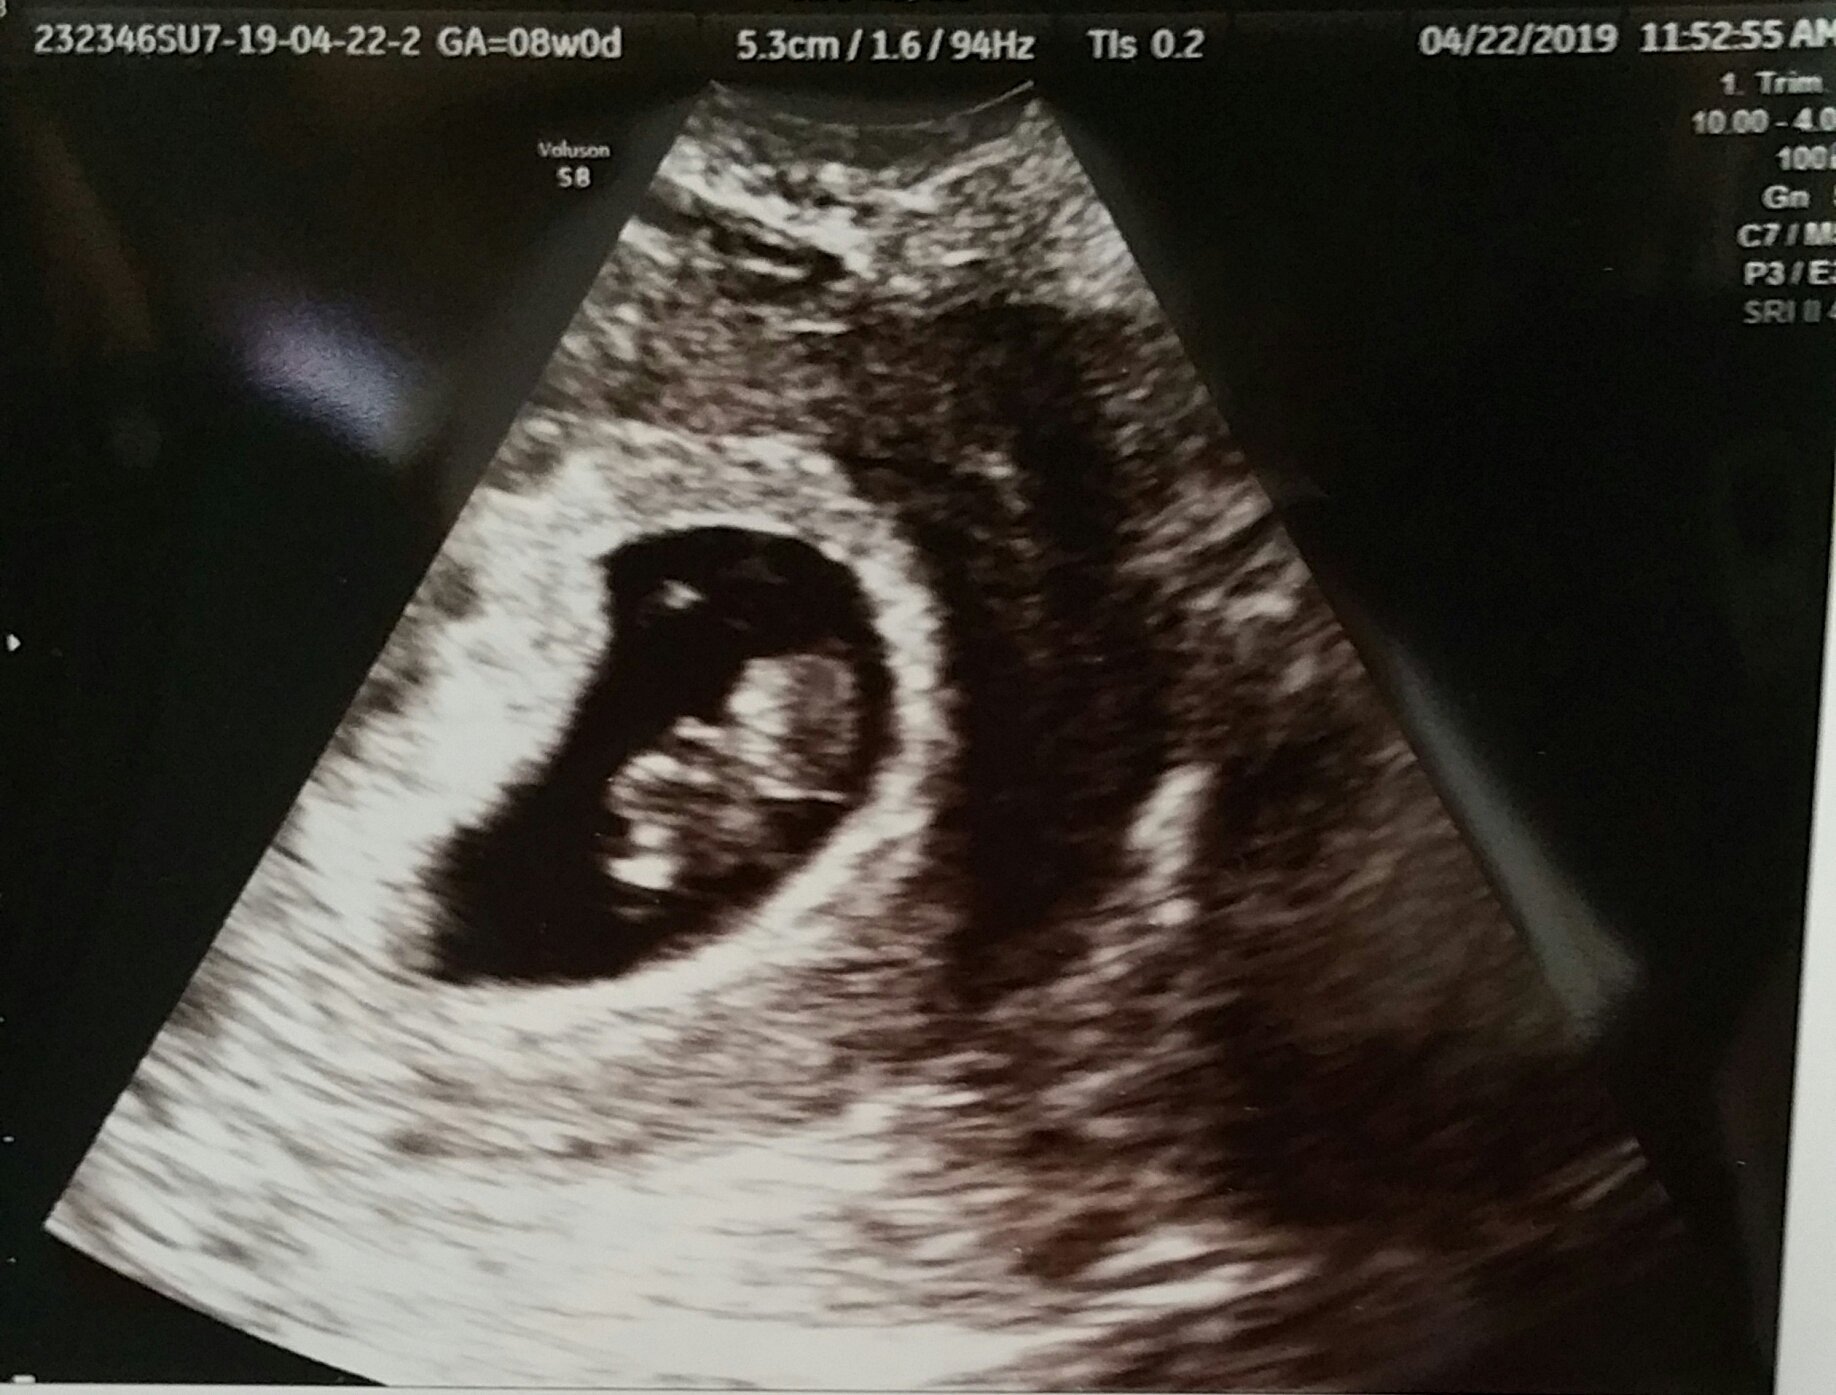

(Taken from June 2019)

Found out yesterday, I am having twins.. EDD 12.7.19